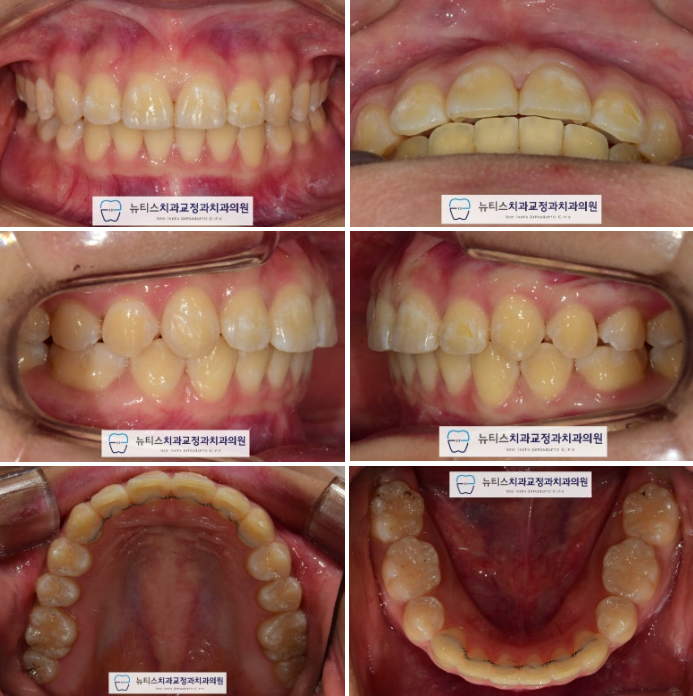

ÃÊÁø »çÁøÀÔ´Ï´Ù.

µ¹ÃâµÈ ¾Õ´Ï¿Í »ß¶Ô¾îÁø Ä¡¾Æ¸¦ º¸ÀÔ´Ï´Ù.

»ó¾Ç Á¦ 1 ´ë±¸Ä¡´Â À̰¡ ½â¾î¼

¸Ó¸®ºÎºÐÀÌ ¾ó¸¶³²Áö ¾Ê¾Ò½À´Ï´Ù.